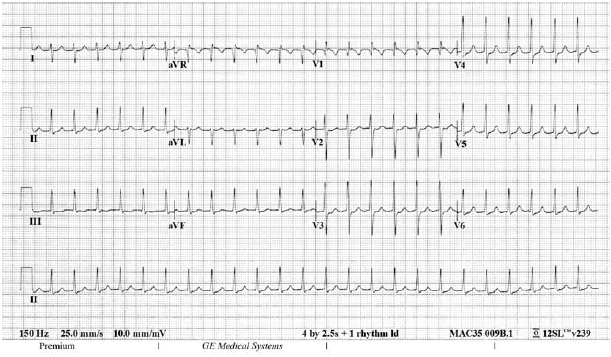

Uma jovem de vinte e dois anos de idade, previamente hígida, ingressou no pronto-socorro apresentando um quadro de palpitações taquicárdicas, de início súbito, havia uma hora. Ela negou outros sinais ou sintomas. Ao exame físico, a paciente apresentava-se eupneica e acianótica, em bom estado geral, com pressão arterial de 116 mmHg × 72 mmHg, frequência respiratória de 24 irpm, frequência cardíaca de aproximadamente 150 bpm e ritmo cardíaco regular em dois tempos e sem sopros. Não foram constatadas outras alterações. O seguinte eletrocardiograma (com calibração padrão) mostrado na figura foi realizado na sua chegada ao serviço de pronto atendimento.

No que diz respeito a esse caso clínico, julgue o item subsecutivo.

O tratamento inicial de escolha para a paciente do caso clínico em questão consiste na administração intravenosa de amiodarona.

Recomenda-se, para essa paciente, o uso de ácido acetilsalicílico para a prevenção de eventos tromboembólicos após a reversão da arritmia.